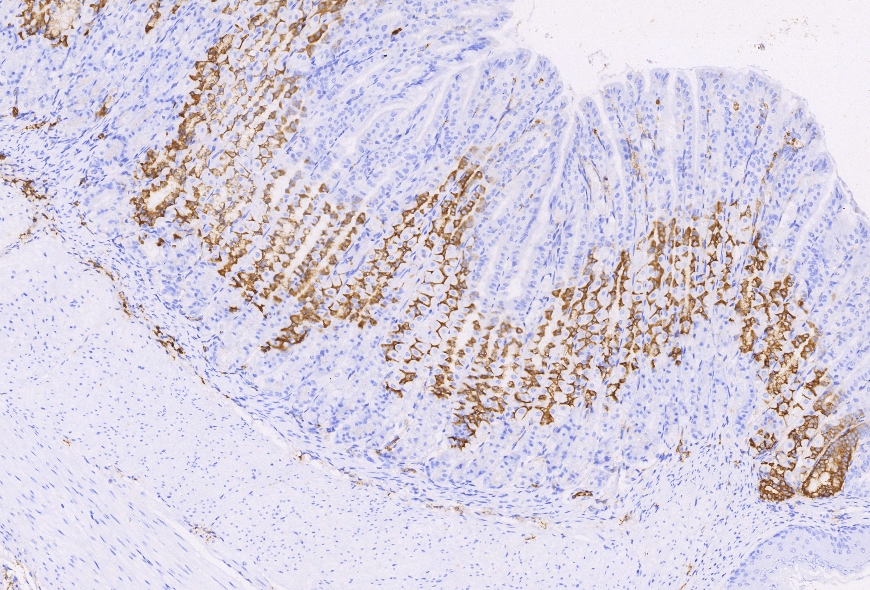

多重荧光免疫组化

多重荧光免疫组化系列产品